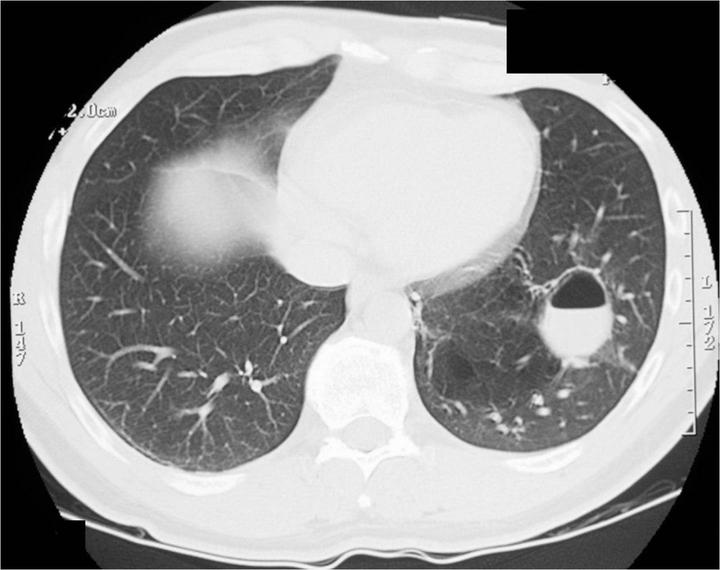

Диагностика

Как диагностировать туберкулёз на раннем этапе? Первоначальный и эффективный метод диагностики проводится в поликлинике во время флюорографии. Она проводится каждому больному раз в год. Флюорография при туберкулёзе выявляет свежие и застарелые очаги в виде инфильтрации, очага или каверны.

Важным методом обследования на обнаружение палочки Коха является посев мокроты на туберкулёз. Микобактерии в посеве выявляются почти всегда, если на рентгенограмме видна каверна. При инфильтрате в лёгких палочка Коха обнаруживается при посеве только в 2% случаев. Более информативен 3 кратный посев мокроты.

Туберкулез протекает в открытой и закрытой формах. Заразна только первая. В этом случае в мокроте больного присутствуют бактерии, и он способен передать палочку еще 10-15 людям. В противотуберкулезном диспансере проводят анализ, в ходе которого выявляют, есть ли в мокроте больного бациллы и является ли он опасным для окружающих. Выявить заболевание возможно и с помощью флюорографии, рентгена или компьютерной томографии.